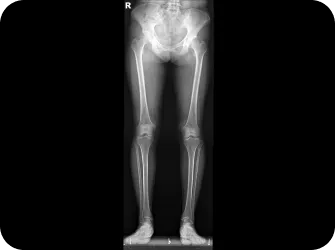

전신 엑스레이 검사

턱, 어깨 높이, 골반 틀어짐, 부정렬

다리길이 엑스레이 검사

다리 길이 차이에 의한 목과 안면비대칭 파악

인체는 바이오링크에 의해 모두 연결되어 있습니다.

발목과 무릎처럼 서로 가까이서 영향을 주고 받기도 하지만

어깨뼈와 후두골, 천골(골반사이삼각형뼈)-목뼈2번-턱관절처럼

서로 멀리 떨어진 뼈들이 밀접하게 연관되어 움직이기도 합니다.

골반 틀어짐도 안면비대칭을 악화시키는 요인이 되기 때문에 비틀린 골반을 정상화하여 몸 전체의 축을 바로 잡으면 얼굴비대칭의 개선 뿐만 아니라 피로의 개선 및 목과 허리 골반통증 완화 효과도 있습니다.